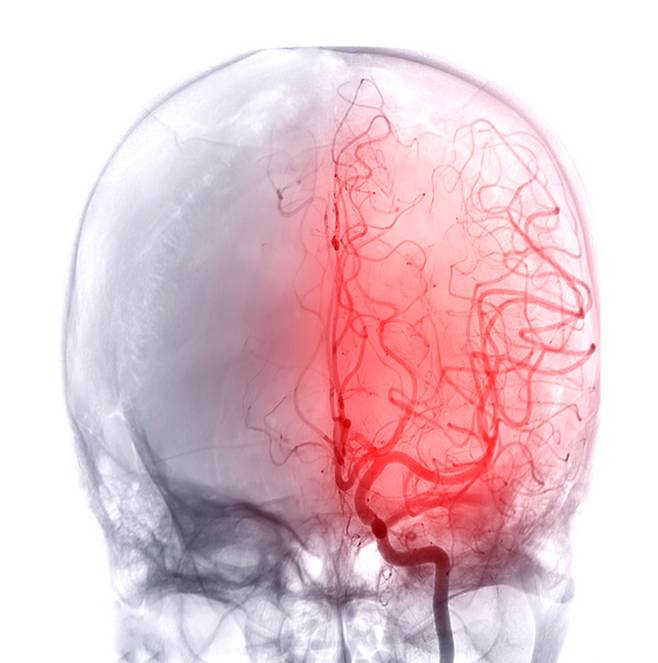

10일 질병관리청 국가건강정보포털 및 심뇌혈관질환 통계에 따르면 국내 뇌졸중 발생 건수는 11만3098건(2023년 기준)이다. 발생 후 1년 내 치명률은 19.8%로 집계됐다.

하루 평균 300명 이상. 일상 속 누구에게나 벌어질 수 있는 수준이다. 국내 조사 기준 뇌졸중 조기 증상 인지율은 60%대에 머물렀다.

상당수가 초기 경고 신호를 놓칠 가능성이 있다는 의미다. 결국 생사를 가르는 건 ‘지속 시간’이 아닌, 처음 나타난 이상을 어떻게 받아들였느냐다.

◆사라졌다고 끝 아니다…48시간이 갈림길

이 짧은 증상의 정확한 명칭은 ‘일과성 허혈 발작(TIA)’이다. 일시적으로 뇌로 가는 혈류가 감소하거나 차단됐다가 회복되는 상태를 말한다. 쉽게 말해 ‘잠깐 지나간 뇌졸중’처럼 보이지만, 실제로는 더 큰 사고의 전조일 수 있다.

겉으로는 멀쩡해 보여도 위험이 사라진 것은 아니다. 혈관 내부의 문제는 그대로 남아 있을 가능성이 크다.

대한뇌졸중학회는 이를 뇌졸중의 명확한 전조로 보고, 증상이 회복됐더라도 즉시 병원을 찾아야 한다고 강조한다.

해외 연구에서도 일과성 허혈 발작 이후 90일 내 뇌졸중 발생 위험은 10~20% 수준으로 보고된다. 특히 발작 직후 ‘첫 48시간’이 가장 위험한 구간으로 꼽힌다.

서울 소재 대학병원 신경과 전문의는 “증상이 일시적으로 회복됐더라도 혈관 속 원인은 그대로 남아 있을 수 있다”며 “단 한 번이라도 이상을 느꼈다면 지체 없이 병원을 찾아야 한다”고 말했다.